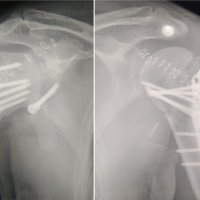

Case Report: The authors report a case of chondroblastoma involving the diaphyseal area of radius in a seven year old female child. She presented with pain and swelling around the left distal third forearm for eight months . Wide excision of tumor was performed and the defect was bridged with avascular fibular auto graft , secured to host bone with k-wires and dynamic compression plate to achieve osteosynthesis.